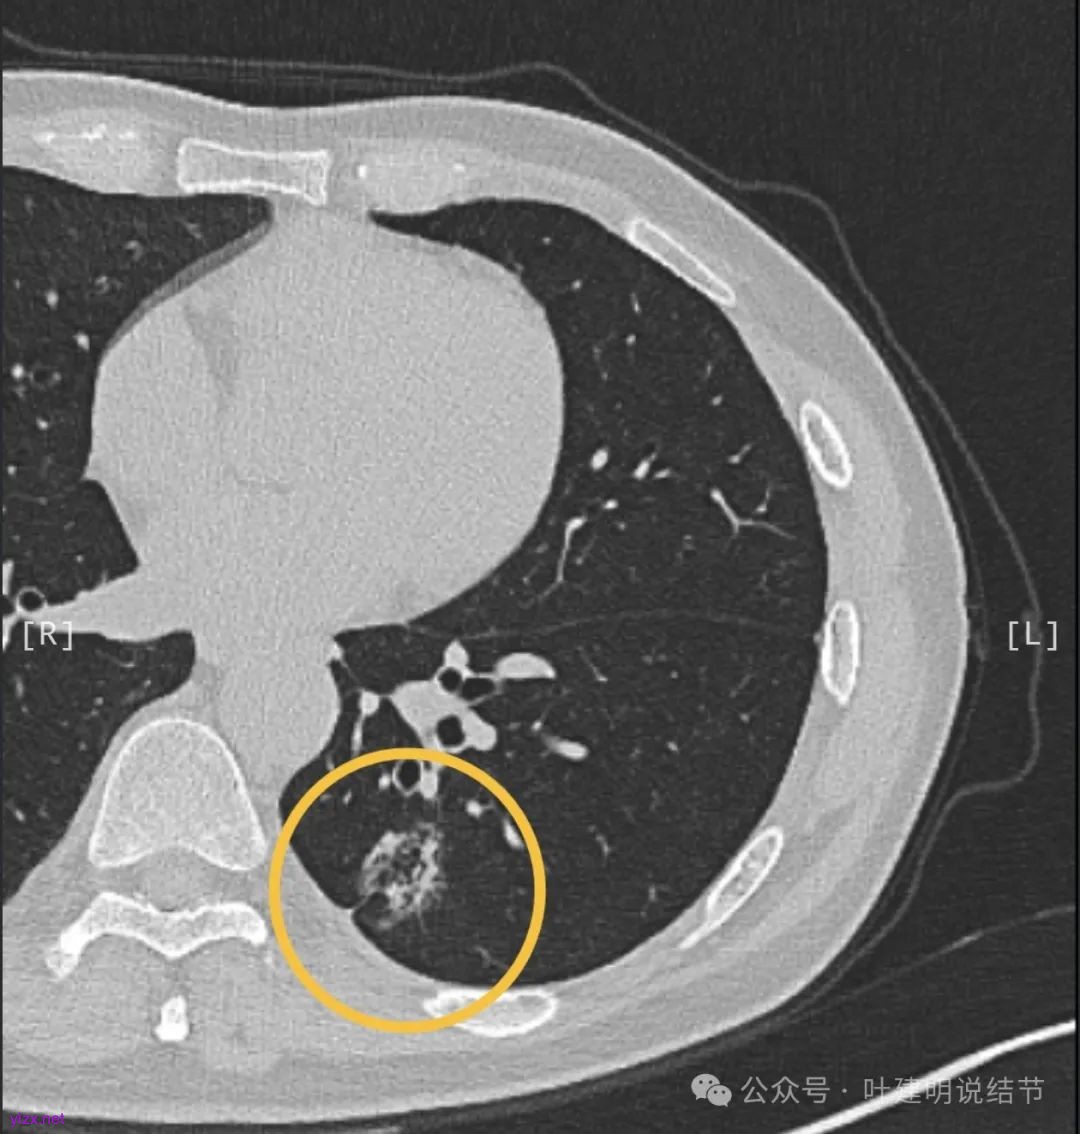

诊断肺结节的性质,有时候术前影像是能够判断八九不离十的,我们不能总想着特例,而应该从普遍更常见的角度去考虑问题。有位肺结节患者向我网络咨询了三次,过年前我就说年后尽快要手术,结果犹豫当中还是拖了一段时间。当然最后还是去开了,术中病理居然报的是不典型增生!这怎么可能呢?我告诉他常规病理肯定会升级。现在结果反馈来了。

第1次问诊的时候,我就说这个病灶考虑是浸润性腺癌,但是由于合并存在局灶支气管扩张,所以不能100%确认。但是建议他年后找时间早点手术切了。

第3次问诊的时候,患者告诉我已经在当地一个很大的医院(全国非常著名)做了手术,术中病理报的是肺泡上皮不典型增生,倾向腺癌。我不知道这是个怎样的诊断,到底是不典型增生还是腺癌。但是我认为术后病理是会升级的,由于磨玻璃成分为主,实性成分占比比较少,所以我当时考虑即使升级也是高分化浸润性腺癌可能性大。

最近反馈给我的信息,常规病理果然升级了,但是有所意外的是,高危亚型占5%。贴壁亚型只有15%。当然这也符合之前总结的,囊腔型病灶如果是浸润性癌,容易含有低分化成分。